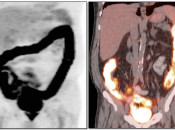

After the stomach, normal intense colon uptake is the most over-called “abnormality” by the inexperienced PET/CT radiologist.

The colon — focally or diffusely — often demonstrates intensely uptake of FDG.

Proposed mechanisms for colonic uptake of FDG include muscle contractions, the presence of lymphoid tissue and intraluminal contents.

The most common sites of normal physiologic intense colon uptake are the cecum and the distal rectum.

Generally, colonic uptake should be considered normal unless:

- There is an accompanying CT abnormality (e.g. focal bowel wall thickening or focal mass); or

- A solitary focus of intense uptake presents in an otherwise non-avid (or minimally avid) colon. Although this focal uptake may still represent normal physiologic uptake, it is reasonable to raise the possibility of a small polyp and recommend colonoscopy (polyps are rarely visible on the CT images).

We generally report, “As an adenomatous polyp or other pathology cannot be excluded, further evaluation with colonoscopy may be warranted, if not recently performed.”